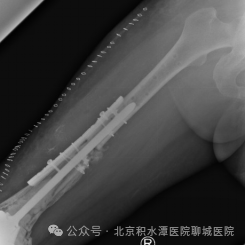

下肢X线片

应用3D打印骨整合钛板+cone+定制延长杆行膝关节翻修术。

股骨远端骨缺损严重

3D打印骨整合钛板加强骨折断端增加稳定